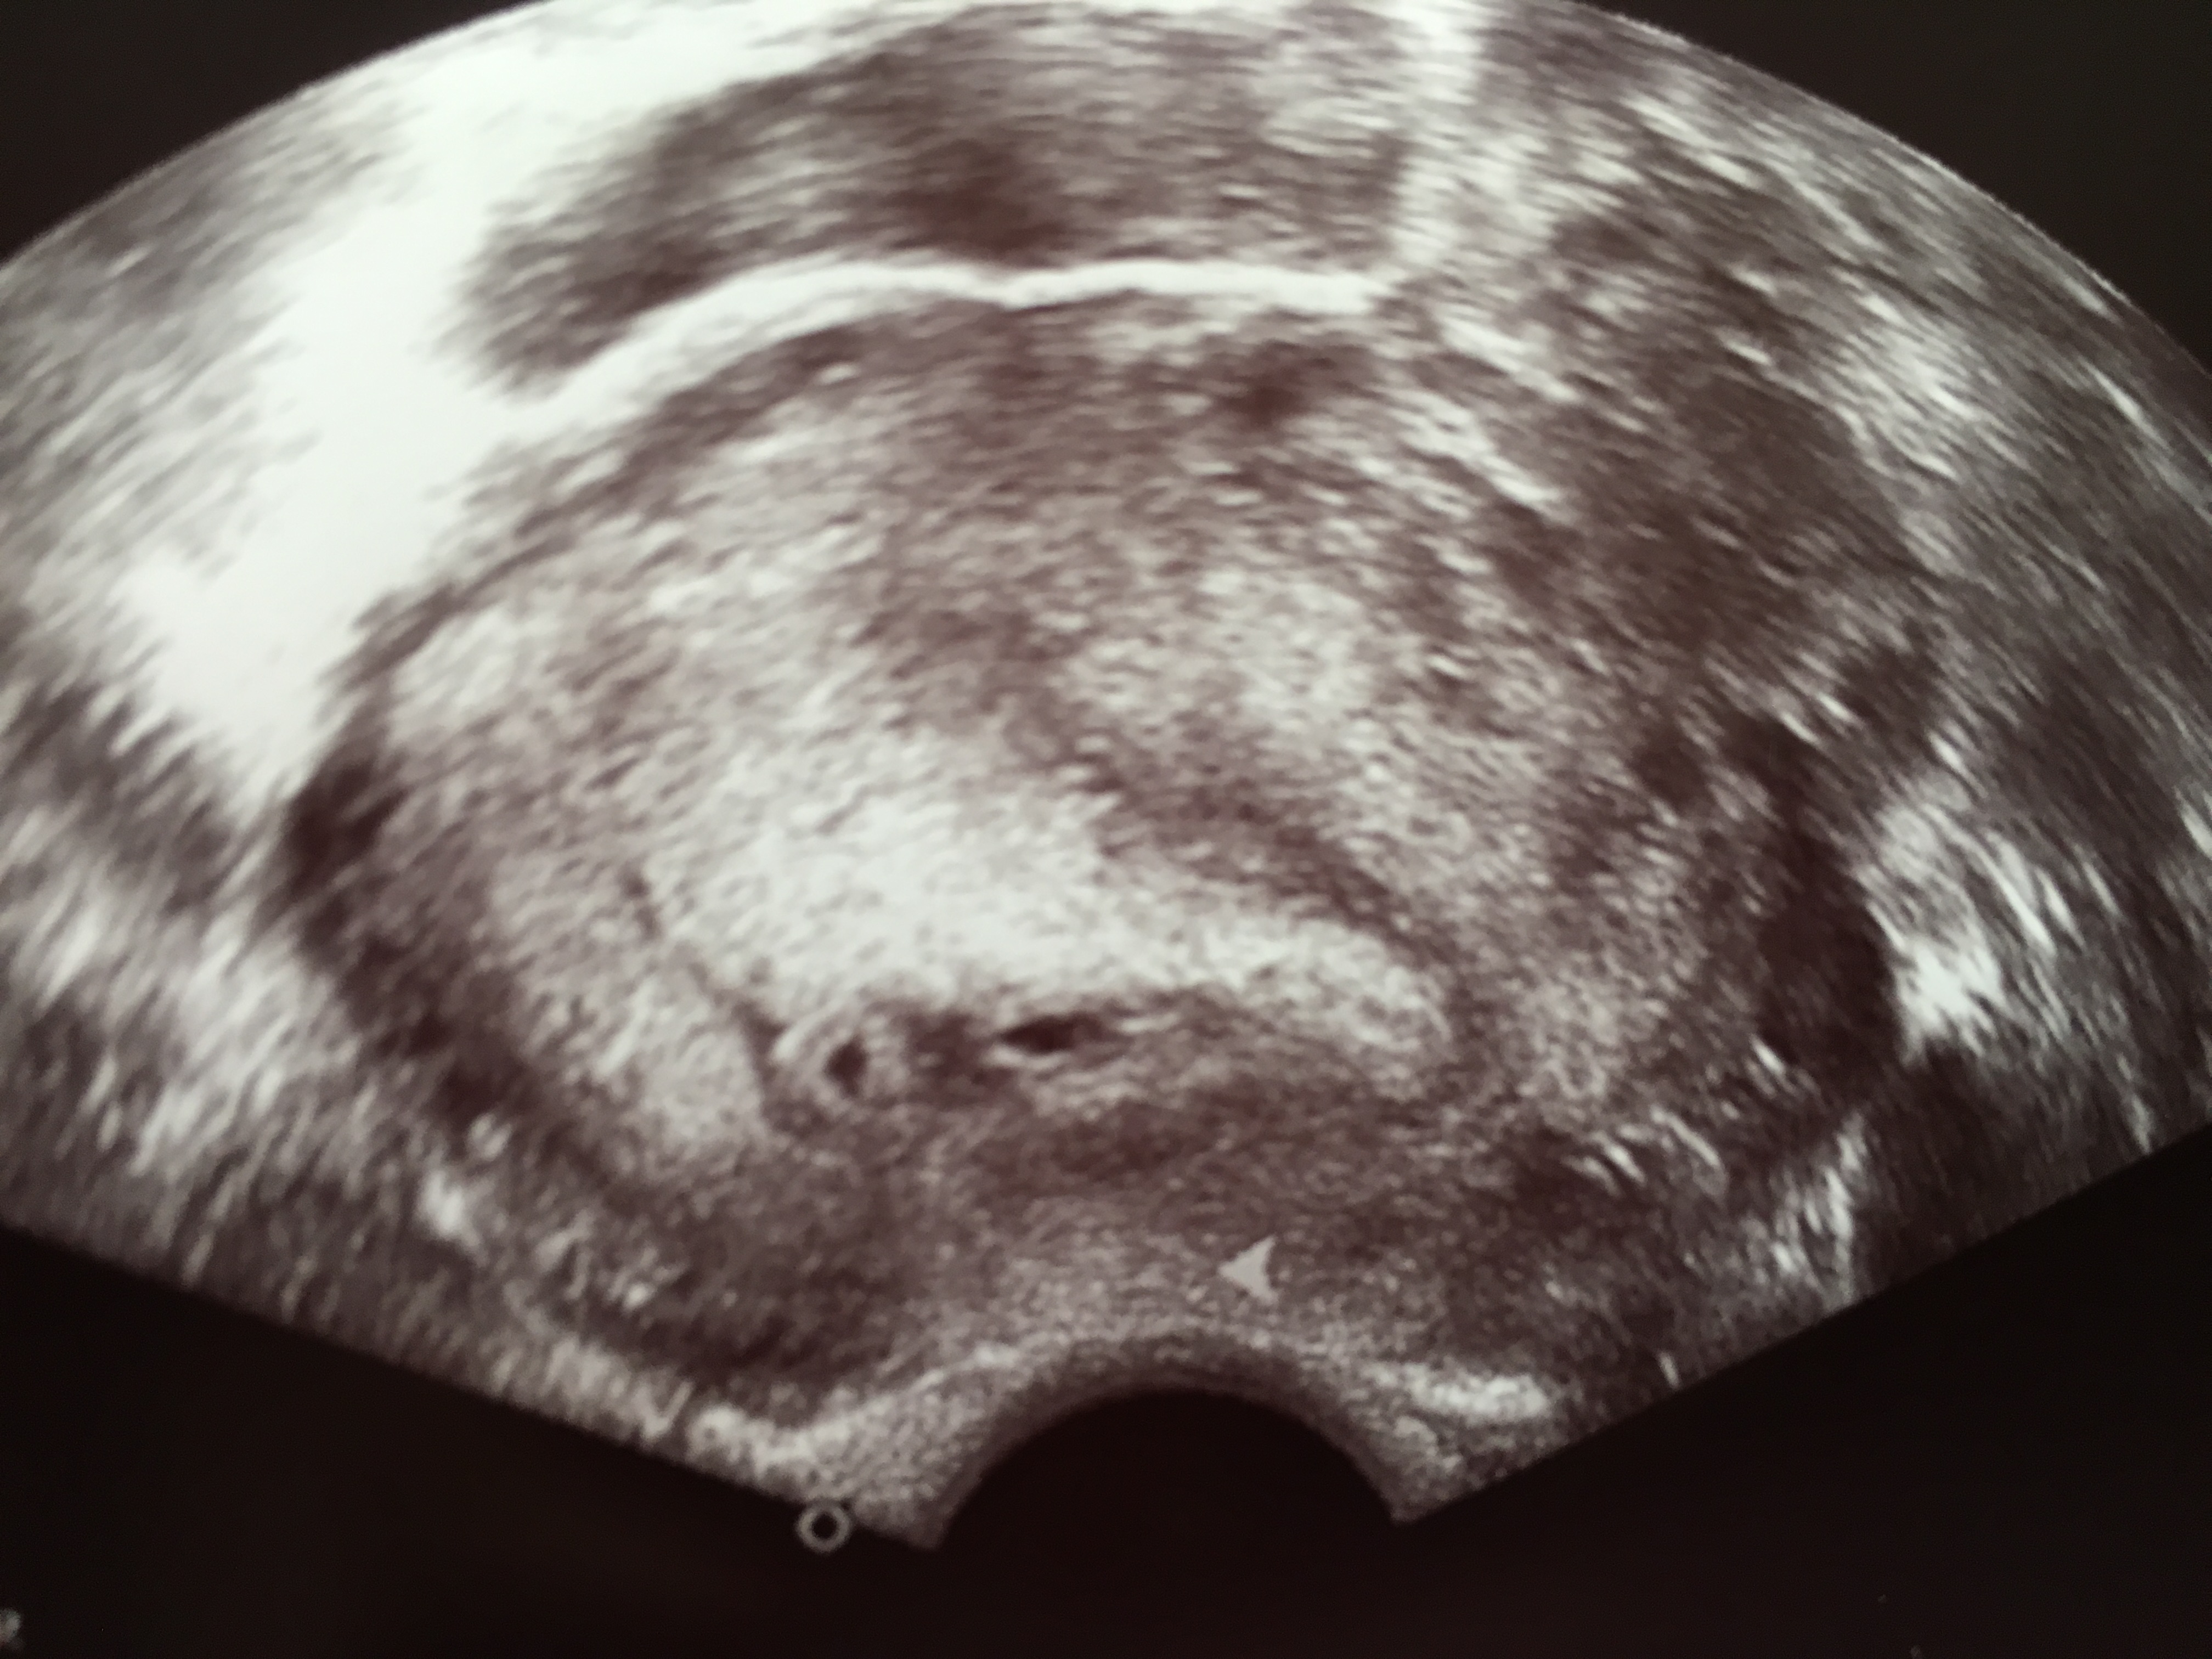

5 2 Ssw Schwangerschaft Ultraschall

Ultraschallbild Ssw 5 2 Schwangerschaft